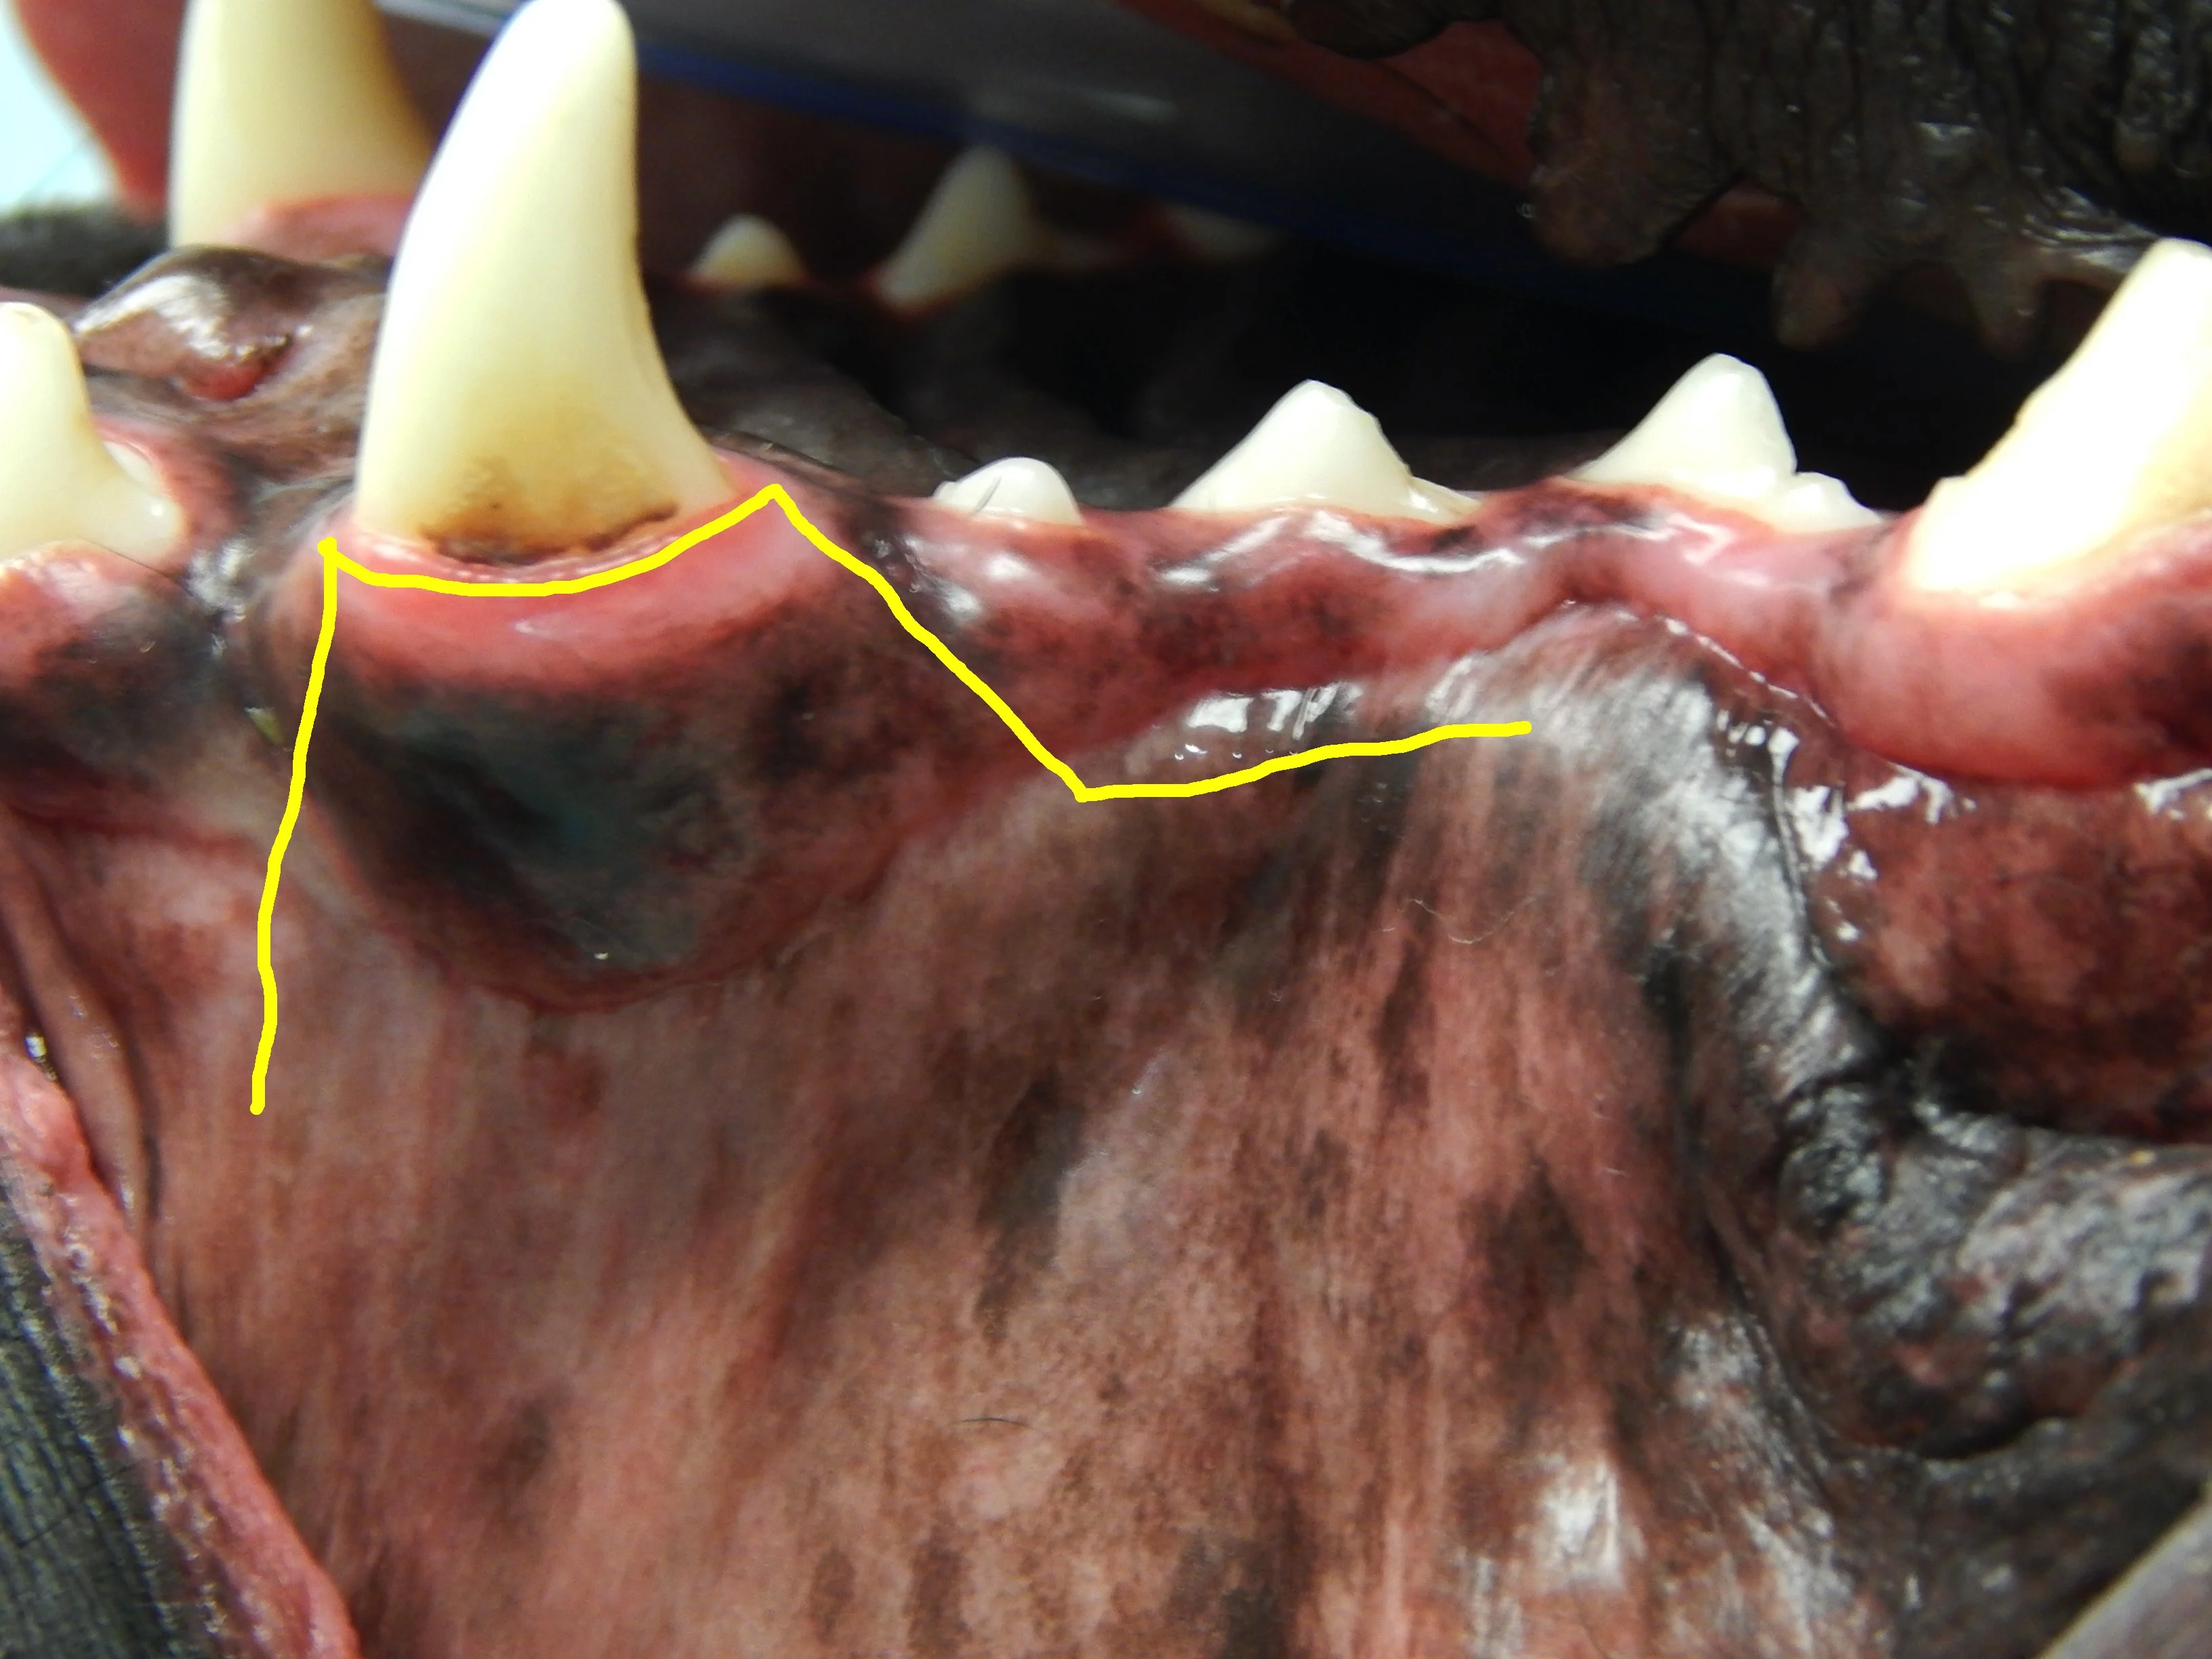

Closing a mucogingival flap under tension increases the risk for dehiscence,4 and understanding the options available for complete flap mobilization (eg, proper release of the periosteum, preplanning advancement flap design, releasing incision placement) is important when reducing tension on a flap. Damaged tissue should be removed prior to closure of the wound. Patients with severe periodontal disease can have significant loss of the buccal-attached gingiva and mucosa (Figure 3). Tissue that is lost, either due to pre-existing disease or surgical trauma, makes closure of a gingival flap more difficult.

Calculus accumulation and significant loss of the attached gingiva (arrows) of the left maxillary canine tooth. Gingival recession can make surgical closure more difficult and increase the potential for postoperative complications.